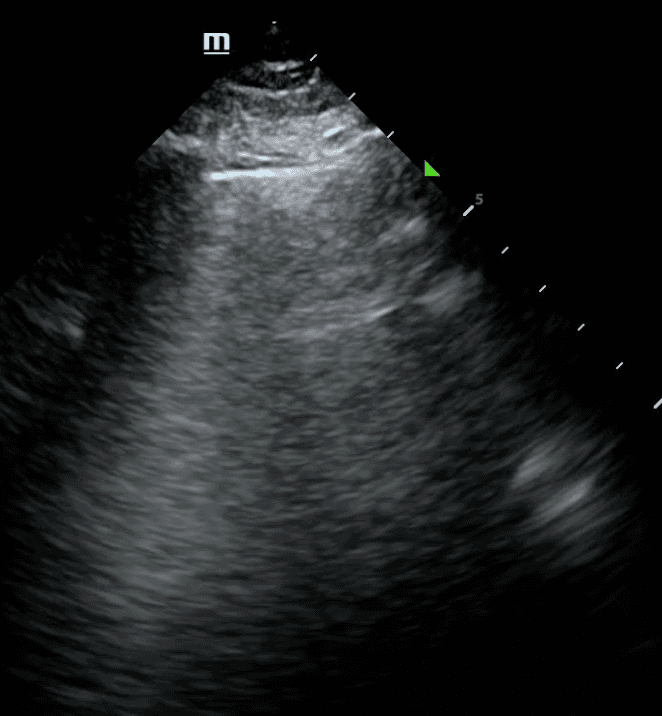

Pleural line abnormalities are another relevant marker in diagnosis lung disease. A normal pleura is thin and smooth. A thick or irregular pleural line is usually due to inflammatory conditions, such as pneumonia. However, the pleura in non-inflammatory diseases, like congestive heart failure, is often smooth and thin.

Other lung ultrasound features such as subpleural consolidation, shred sign and dynamic air bronchograms can point to inflammatory conditions including pneumonia or ARDS. One of the earliest lung ultrasound findings of pneumonia is that of localized B lines with small areas of subpleural consolidation due to loss of air-filled lung. Learn more about consolidations here.